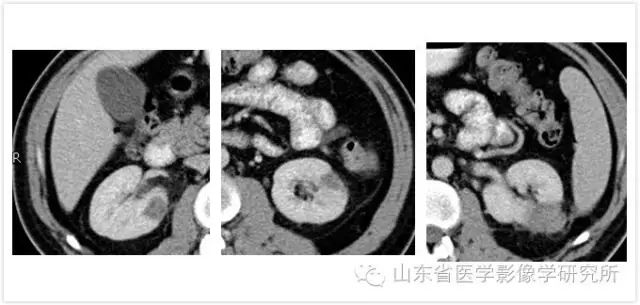

患者男性,38岁。 体检发现左肾占位。 进一步CT检查发现双肾共3个肿瘤。 影像学检查与肾癌表现一致。 这个消息对于事业处于上升期的患者来说是一个巨大的打击。 而且,由于他的双肾都有多个肿瘤,所以没有手术切除的机会。 患者来到我科后,孙耀主任精心制定了治疗方案,并两次对双肾三个肿瘤进行了消融治疗。 所有肿瘤均经病理证实为肾癌。 截至目前,肿瘤未见复发或转移。

▲术前超声检查清晰显示病灶全部

▲术后CT显示所有病灶完全消融